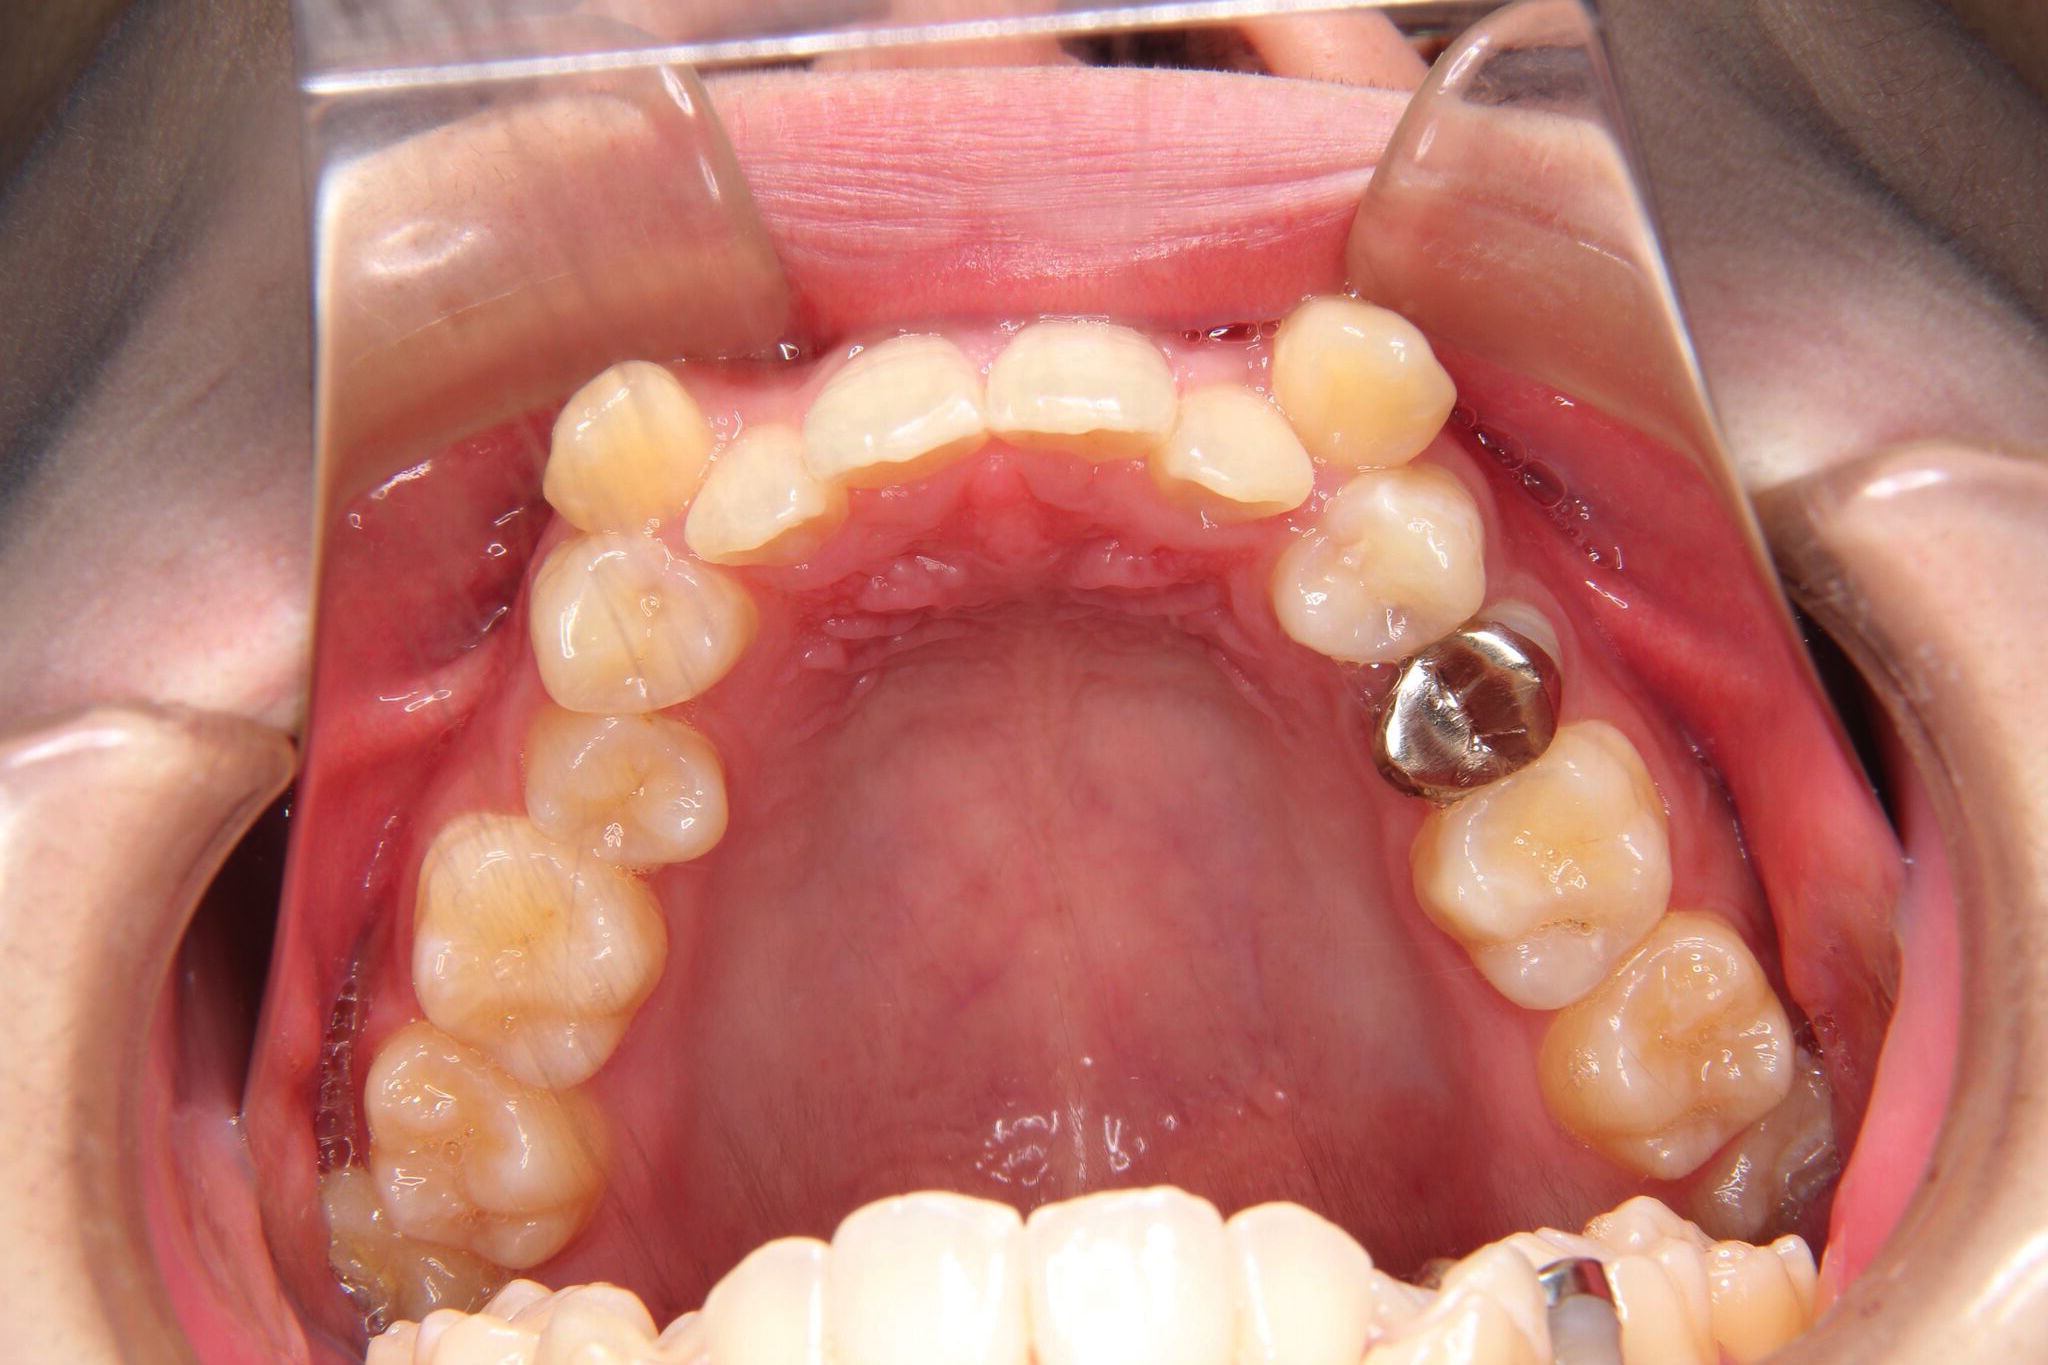

受け口

反対咬合(上顎前歯部叢生)

【患者】 10代 男性

【期間】 1年5カ月

- 治療前 治療後

非抜歯で治療を行いました。

- 上顎大臼歯部の遠心移動

- 下顎歯列全体のアップライティング